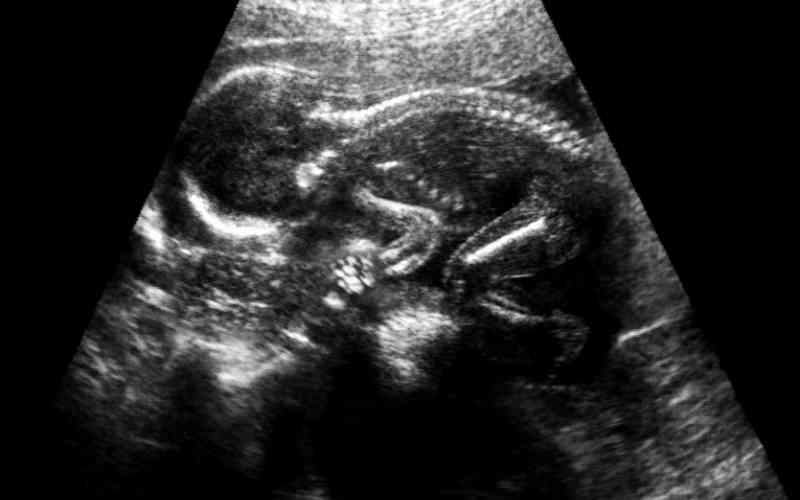

Theo thống kê, tại Việt Nam có khoảng 10-13% phụ nữ mang thai nhiễm virus viêm gan B. Đây là căn bệnh truyền nhiễm có ảnh hưởng nghiêm trọng đến sức khỏe mẹ bầu, đặc biệt là nó có thể lây sang thai nhi. Vì vậy, chúng ta cần biết cách chăm sóc bà bầu bị viêm gan B để giảm thiểu nguy cơ lây bệnh từ mẹ sang con và những biến chứng nguy hiểm xảy ra.

Phụ nữ bị viêm gan B trong giai đoạn mang thai không chỉ tiềm ẩn nguy cơ lây nhiễm sang thai nhi cao mà còn có thể tác động tiêu cực đến sức khỏe của cả mẹ và bé. Chúng ta cần nắm rõ những ảnh hưởng đó là gì để biết cách chăm sóc bà bầu bị viêm gan b đúng cách và an toàn nhất.

Bệnh viêm gan B ảnh hưởng đến thai nhi

Virus viêm gan B trú ngụ chủ yếu trong máu và dịch âm đạo của phụ nữ đang mang thai. Vì vậy, bệnh sẽ không lây truyền sang em bé thông qua nhau thai và không cản trở sự phát triển của thai nhi. Do đó, mẹ bầu hoàn toàn không cần phải lo lắng vấn đề mình bị viêm gan B sẽ có nguy cơ sinh con ra mắc dị tật bẩm sinh hoặc phát triển không bình thường,...

Tuy nhiên, trong trường hợp mẹ bầu bị viêm gan B mức độ nặng trong 3 tháng cuối của thai kỳ sẽ làm gia tăng nguy cơ sinh non. Thậm chí tính mạng của mẹ và bé cũng bị đe dọa trong quá trình chuyển dạ.

Đứa trẻ sinh ra từ người mẹ bị nhiễm virus viêm gan B có nguy cơ cao trở thành người mang mầm bệnh và lây bệnh cho người khác. Khi trưởng thành, người đó cũng sẽ phải đối mặt với nguy cơ mắc bệnh xơ gan, ung thư gan từ sớm,...